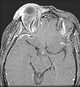

Enlarged superior ophthalmic vein

A carotid-cavernous fistula results from an abnormal communication between the arterial and venous systems within the cavernous sinus in the skull. It is a type of arteriovenous fistula. [Source: Wikipedia ]